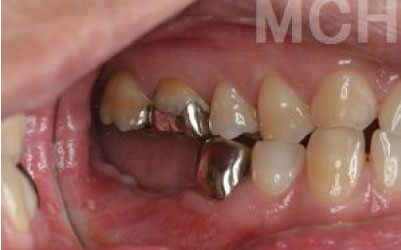

ブリッジとインプラントでは、周囲の歯に与える影響に大きな違いがあります。ブリッジの場合、健康な歯を大きく削る必要があり、さらに通常よりも約1.5倍の咬合力がかかるため、支えとなる歯の寿命が短くなりがちです。実際に、支台歯の約68%が10年以内に抜歯に至るという統計もあります。

ブリッジ治療では、失われた歯の役割を両隣の歯が補うことになるため、その支えの歯には通常の1.5〜2倍ほどの力がかかるとされています。

ブリッジ治療では、欠損部分の両側にある歯を大きく削らなければならず、場合によっては虫歯がなくても歯の神経を抜くことがあります。神経を抜いた歯に被せ物をすると、その歯は急速に弱くなり、寿命が短くなるリスクが高まります。

残っている歯にとって、ブリッジ治療は非常にリスクが高い方法です。

その理由は、ブリッジを作るために隣接する歯を大きく削らなければならないからです。

場合によっては、その歯の神経を取ることもあります。それだけ歯に負担をかけるため、歯の寿命が急激に縮んでしまいます。

最も大きな違いは、前後の歯の寿命に影響が出ることです。

ブリッジの場合、抜けた歯の前後にある歯を、重度の虫歯と同じくらいまで削る必要があります。

また、抜けた歯の代わりに前後の歯が力を支えるため、その歯に常に1.5倍の負荷がかかります。

1)ブリッジ

2)歯を大きく削る+支えの歯に1.5倍の力がかかる

3)前後の歯の寿命が著しく減る

ブリッジの支えの歯は、データでは10年以内に68%が抜歯になります。